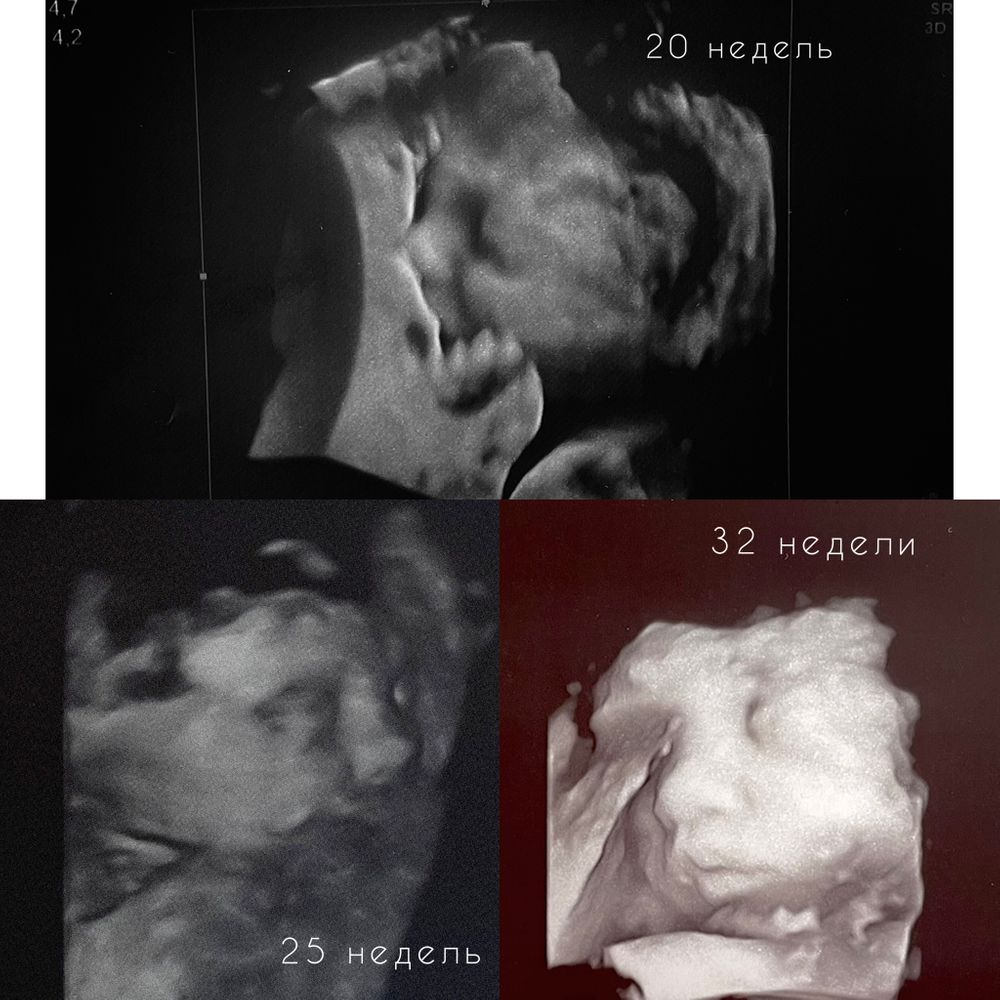

Есть) Вот наши снимки

Первое 3д 28 недель, второе 32 недель, а 3е в 34. Везде все видно, но самое лучшее на 28 неделе, но там ещё и аппарат был крутым, из за этого и более четкое изображение